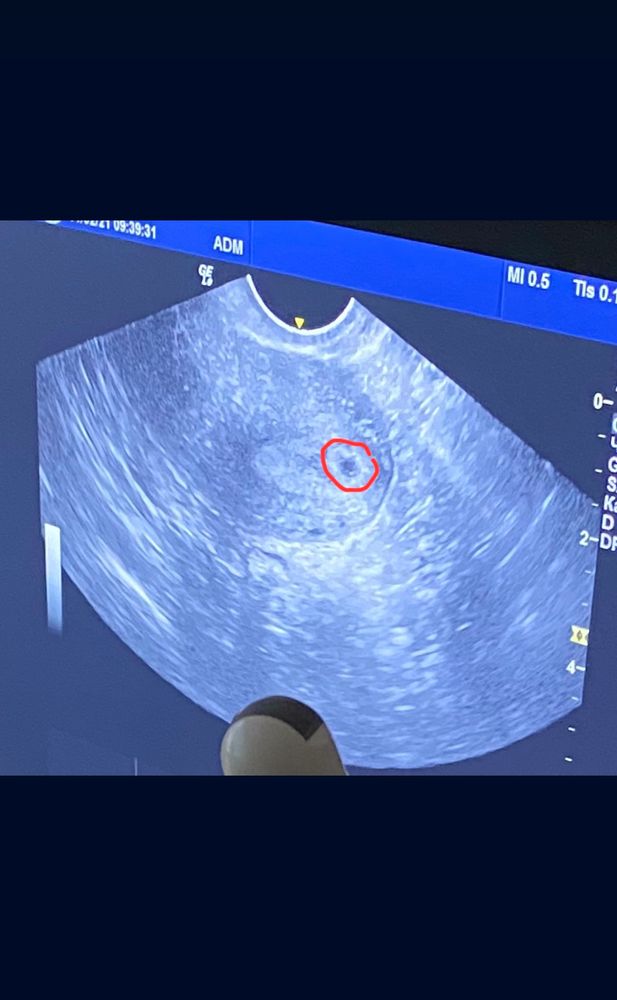

вчера было узи , сказали что в общем видят плодное яйцо и в нем что-то беленькое, видимо эмбрион , я очень переживала , что внематочная !!!!!

но срок до безумия мал , 3-4 недели всего и пя 4 мм.

фото узи есть.